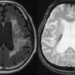

VRで!ガン手術

医療と映像の関連性は、ここ数年でどんどん深くなってきています。そして、その関連性は海外ではさらに加速させていると言えるのです。たとえばイギリスでは、斬新な形で効果的に映像が使われています。